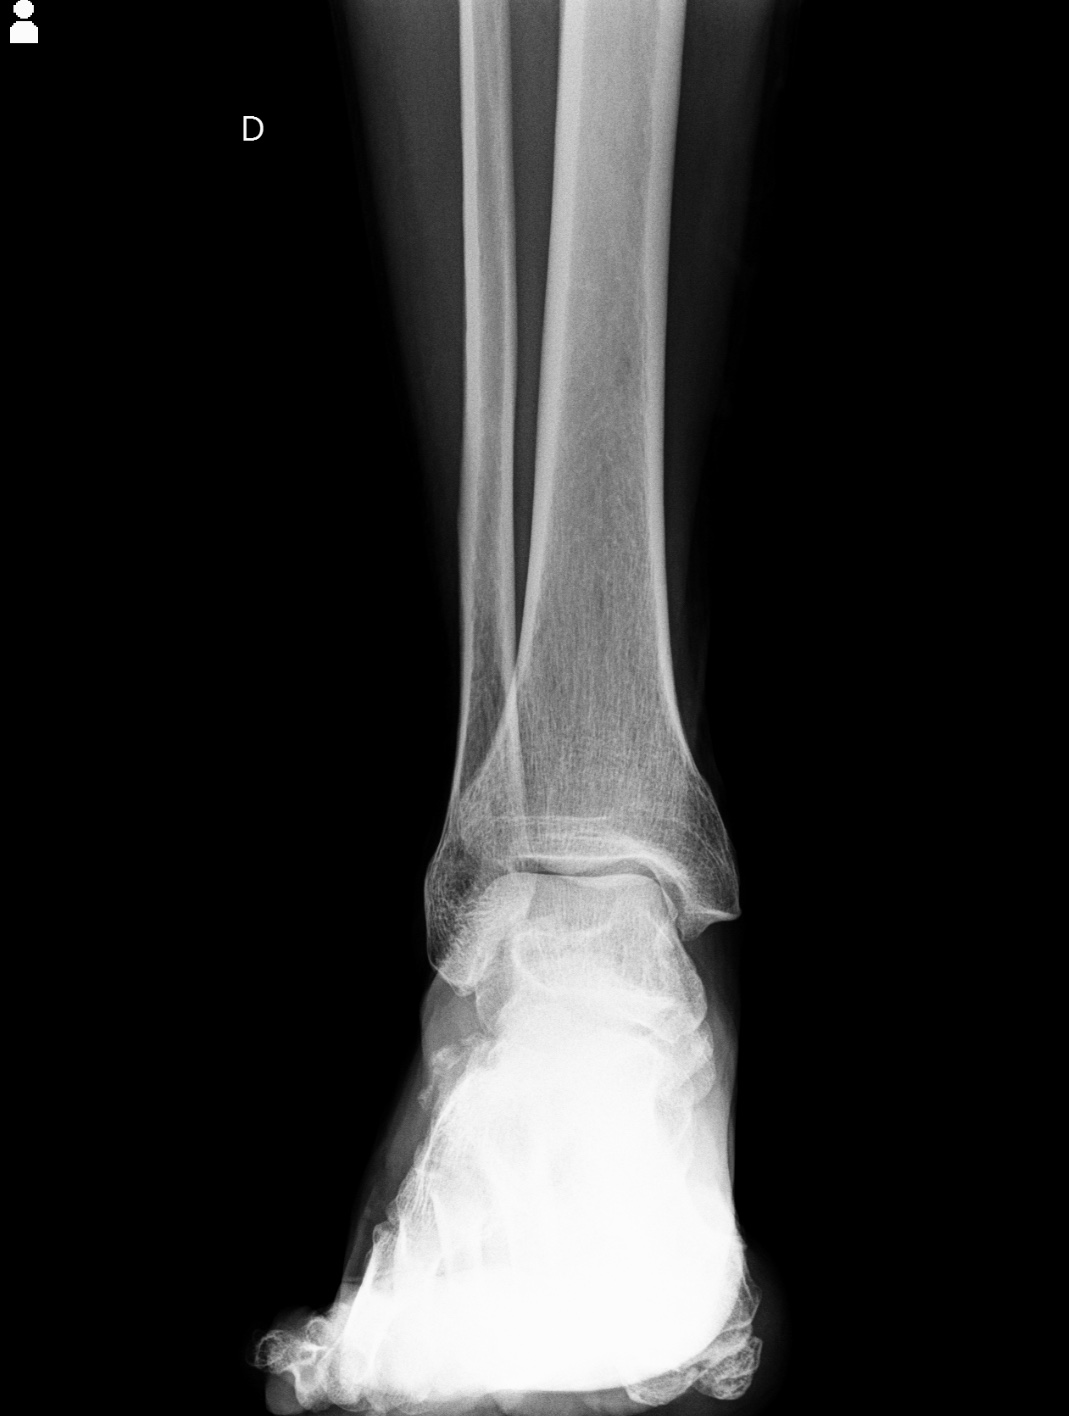

El servicio de Rayos X, se encarga de realizar estudios radiográficos para obtener imágenes del interior del cuerpo humano mediante radiación ionizante. Estas imágenes permiten observar estructuras óseas y algunos tejidos blandos, facilitando el diagnóstico médico de fracturas, infecciones, alteraciones pulmonares, entre otras patologías.

El Hospital CEMA cuenta con personal especializado y equipos digitales que garantizan calidad diagnóstica y seguridad del paciente.